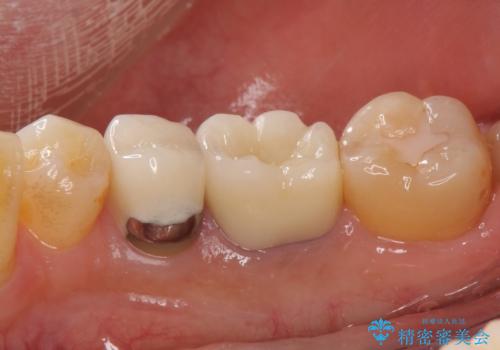

気になっていた銀歯を自然な色に変えることができ、大変喜んでいただけました。

- 右下6 仮歯+ジルコニアクラウン 11,000円+121,000円費用は治療当時の料金となります